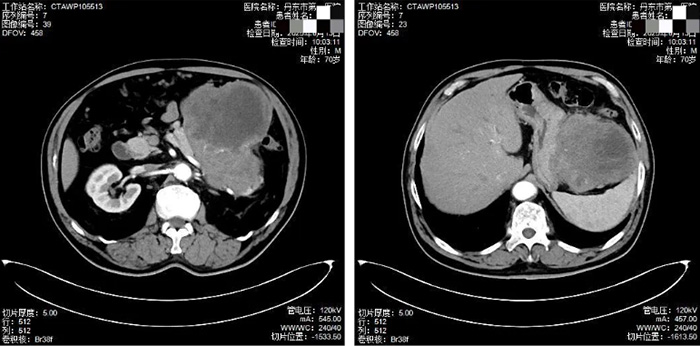

我院普外一科的薛宏威医生接诊后,为刘大爷安排了CT检查。当检查结果出来时,科室见多识广的医生们都在暗自吃惊——刘大爷的腹腔里竟然藏着一个直径接近26厘米的巨型肿瘤,相当于一个小西瓜的大小,严重压迫着胃体、胰腺和脾脏等重要器官。